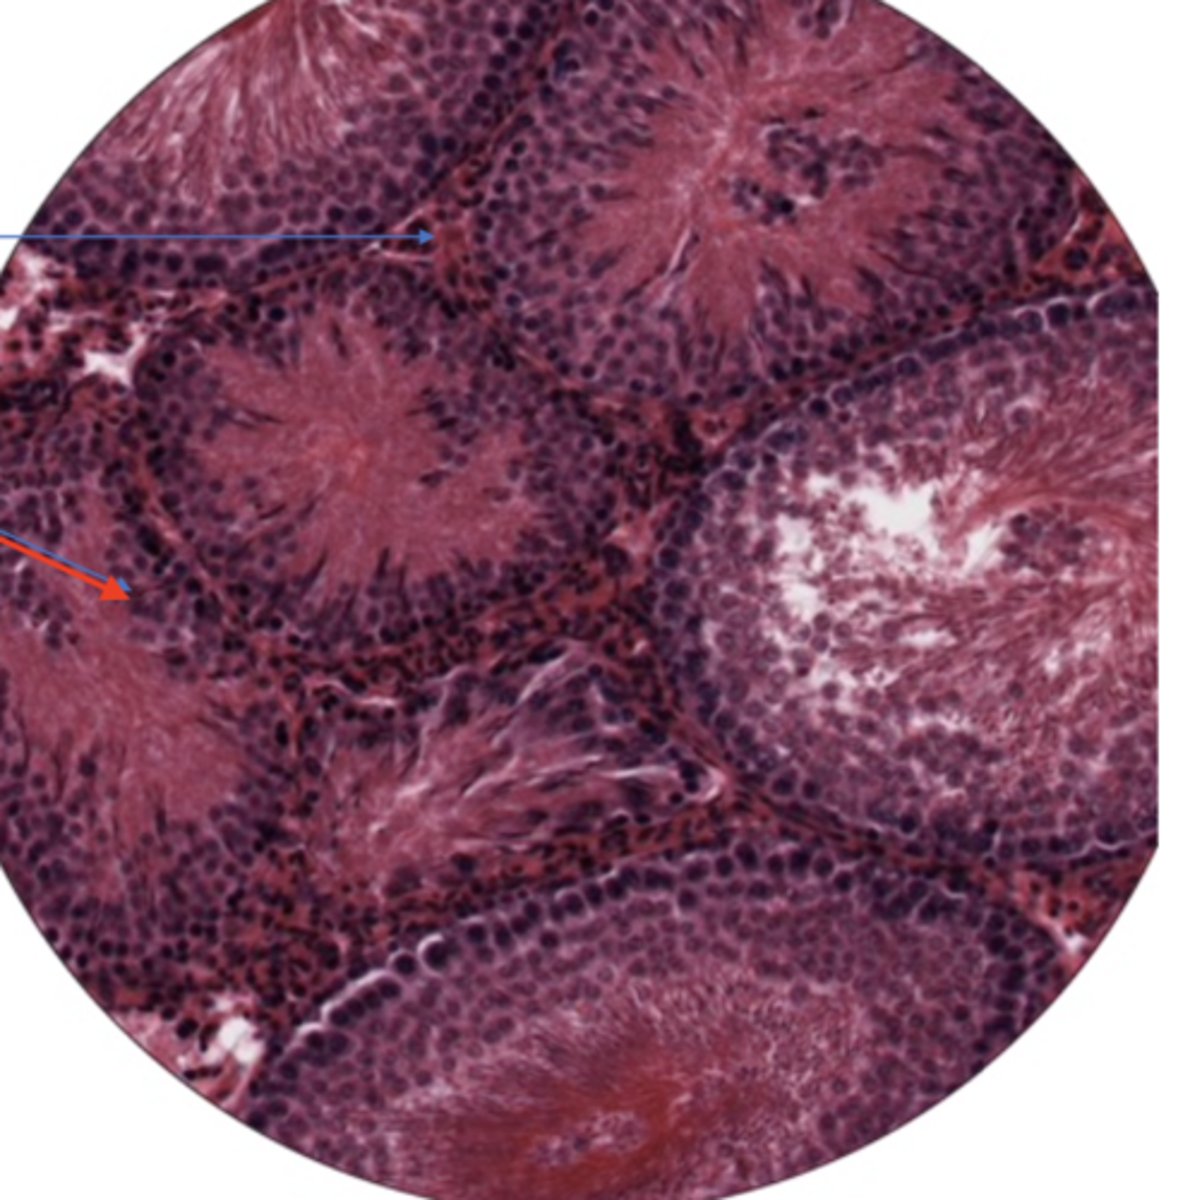

SI mucosa layer (400)

LI mucosa layer (400)